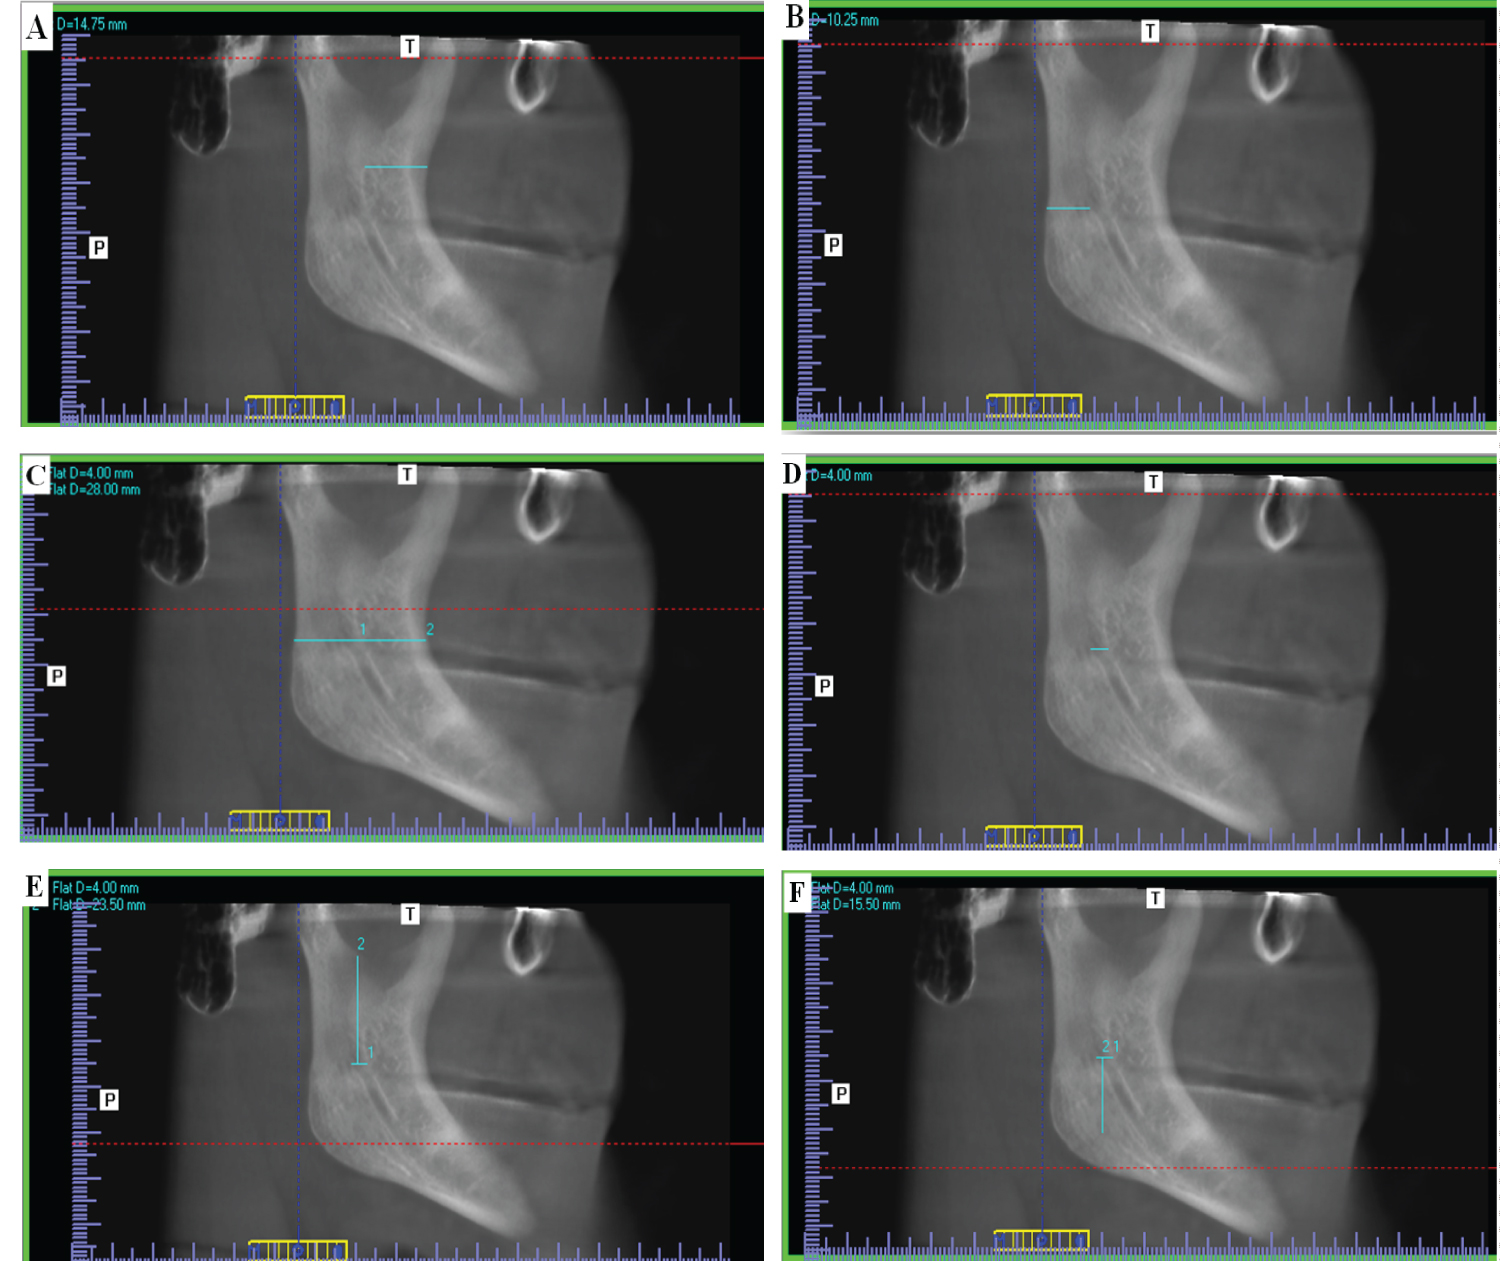

To measure distances AB-MF, PB-MF, RW, CW, MN-MF, MF-IB and RH, standardization was done as follows: In the coronal view, the axial plane was scrolled upwards till reaching the axial slice that shows the beginning of complete separation between mandibular condyle and coronoid processes. In the axial view, the view rotated till the condyle and coronoid became tangent, then the sagittal plane was moved to pass through both the condyle and the coronoid as illustrated in (Figure 1A). In the axial view, the coronal plane was scrolled to attain complete visualization of the mandibular foramen. In the coronal view, the view rotated till MF buccal wall became parallel to sagittal plane, then the sagittal plane was then adjusted to pass through the buccal wall of the mandibular foramen as illustrated in (Figure 1B). Thus, a standardized sagittal view is obtained from which accurate measurements were obtained as illustrated in (Figure 1C).

Figure 1: A) Standardization of axial view on I-CAT Vision software that showed the beginning of complete separation between mandibular condyle and coronoid processes. The axial view was rotated till the condyle and coronoid became on the same plane, and the sagittal plane was moved to pass through both the condyle and the coronoid; B) Standardization of coronal view on I-CAT Vision software that showed the start of complete visualization of the mandibular foramen. The coronal view was rotated till the buccal wall of MF was parallel to the sagittal plane. The sagittal plane was then adjusted to pass through the buccal wall of the mandibular foramen; C) Corrected Sagittal view on I-CAT Vision software was obtained from which accurate measurements can be obtained. View Figure 1

Measurements of AB-MF, PB-MF, RW, CW, MN-MF and MF-IB on the standardized sagittal view are illustrated in (Figure 2A, Figure 2B, Figure 2C, Figure 2D, Figure 2E and Figure 2F) sequentially. The ramus mandibular height (RH) was calculated by adding distances MN-MF and MF-IB from (Figure 2E and Figure 2F).

Figure 2: Corrected sagittal view on I-CAT vision software in a forty-three years dentate female showing the following measurements. A) Distance from midpoint of anterior margin of mandibular foramen to the nearest point on anterior border of ramus of mandible AB-MF; B) Distance from the midpoint of posterior margin of mandibular foramen to the nearest point on the posterior border of the ramus of mandible PB-MF; C) RW; D) Distance from anterior border to posterior border of mandibular foramen passing through midpoint of mandibular foramen CW; E) Distance from the lowest point of mandibular notch to the entering point of mandibular foramen MF-MN; F) Distance from the entering point of mandibular foramen to the point of the greatest convexity of the inferior ramus border MF-IB. View Figure 2